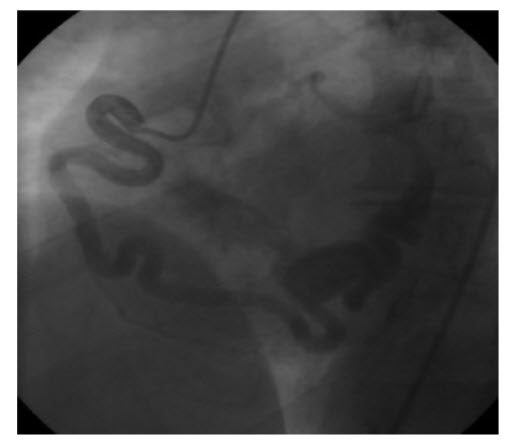

A 65-year-old man with hypercholesterolemia, diabetes, and hypertension presents new, worsening, typical angina symptoms. The angiogram (Fig. below)

shows:

Severe ostial and moderate distal left main trunk stenosis. The coronary angiography shows severe ostial and moderate distal left main trunk stenosis.